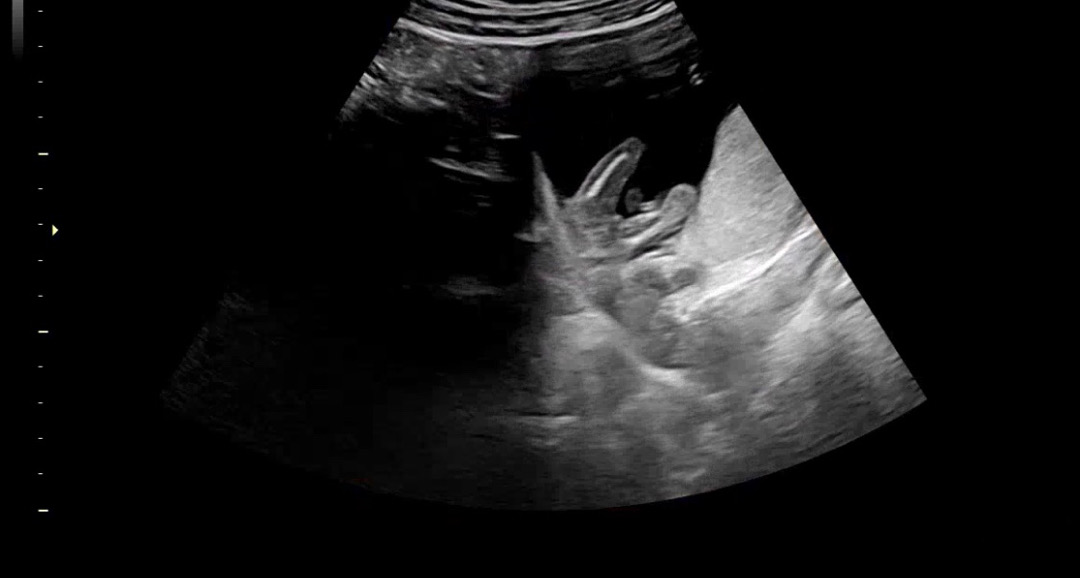

성별이 궁금해여😛

14주 6일차인데 아들일까요 딸일까요?ㅎㅎ

생식기가 퇴화한 정도가 많이된거같아서 딸인듯요

딸같아요

들어가고 있는것 같아요~딸 아닐까요??? 아들은 존재감이 확실해여!! ㅋㅋㅋ

저도 14주 3일차에 아들 확인 했는데 많이 튀어나와있었어요! 저정도면 들어가고 있는것 같은데 정확한건 16주에 볼수 있겠네요 ㅎㅎ